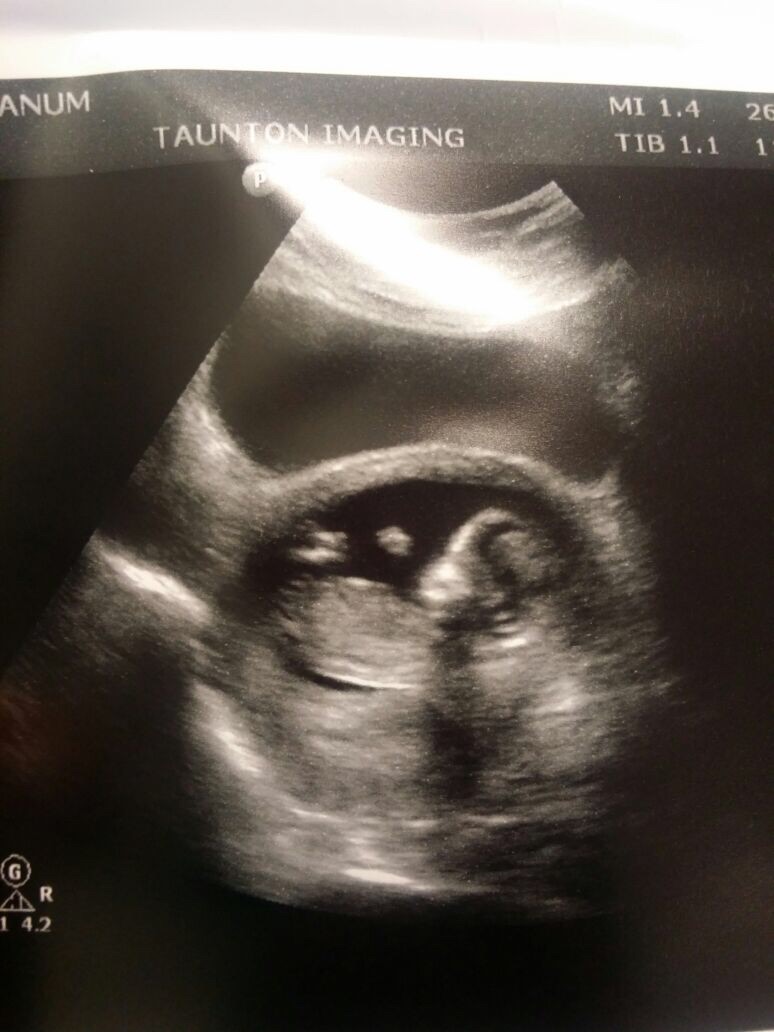

Not sure I can see a nub, sorry. How far along are you? x